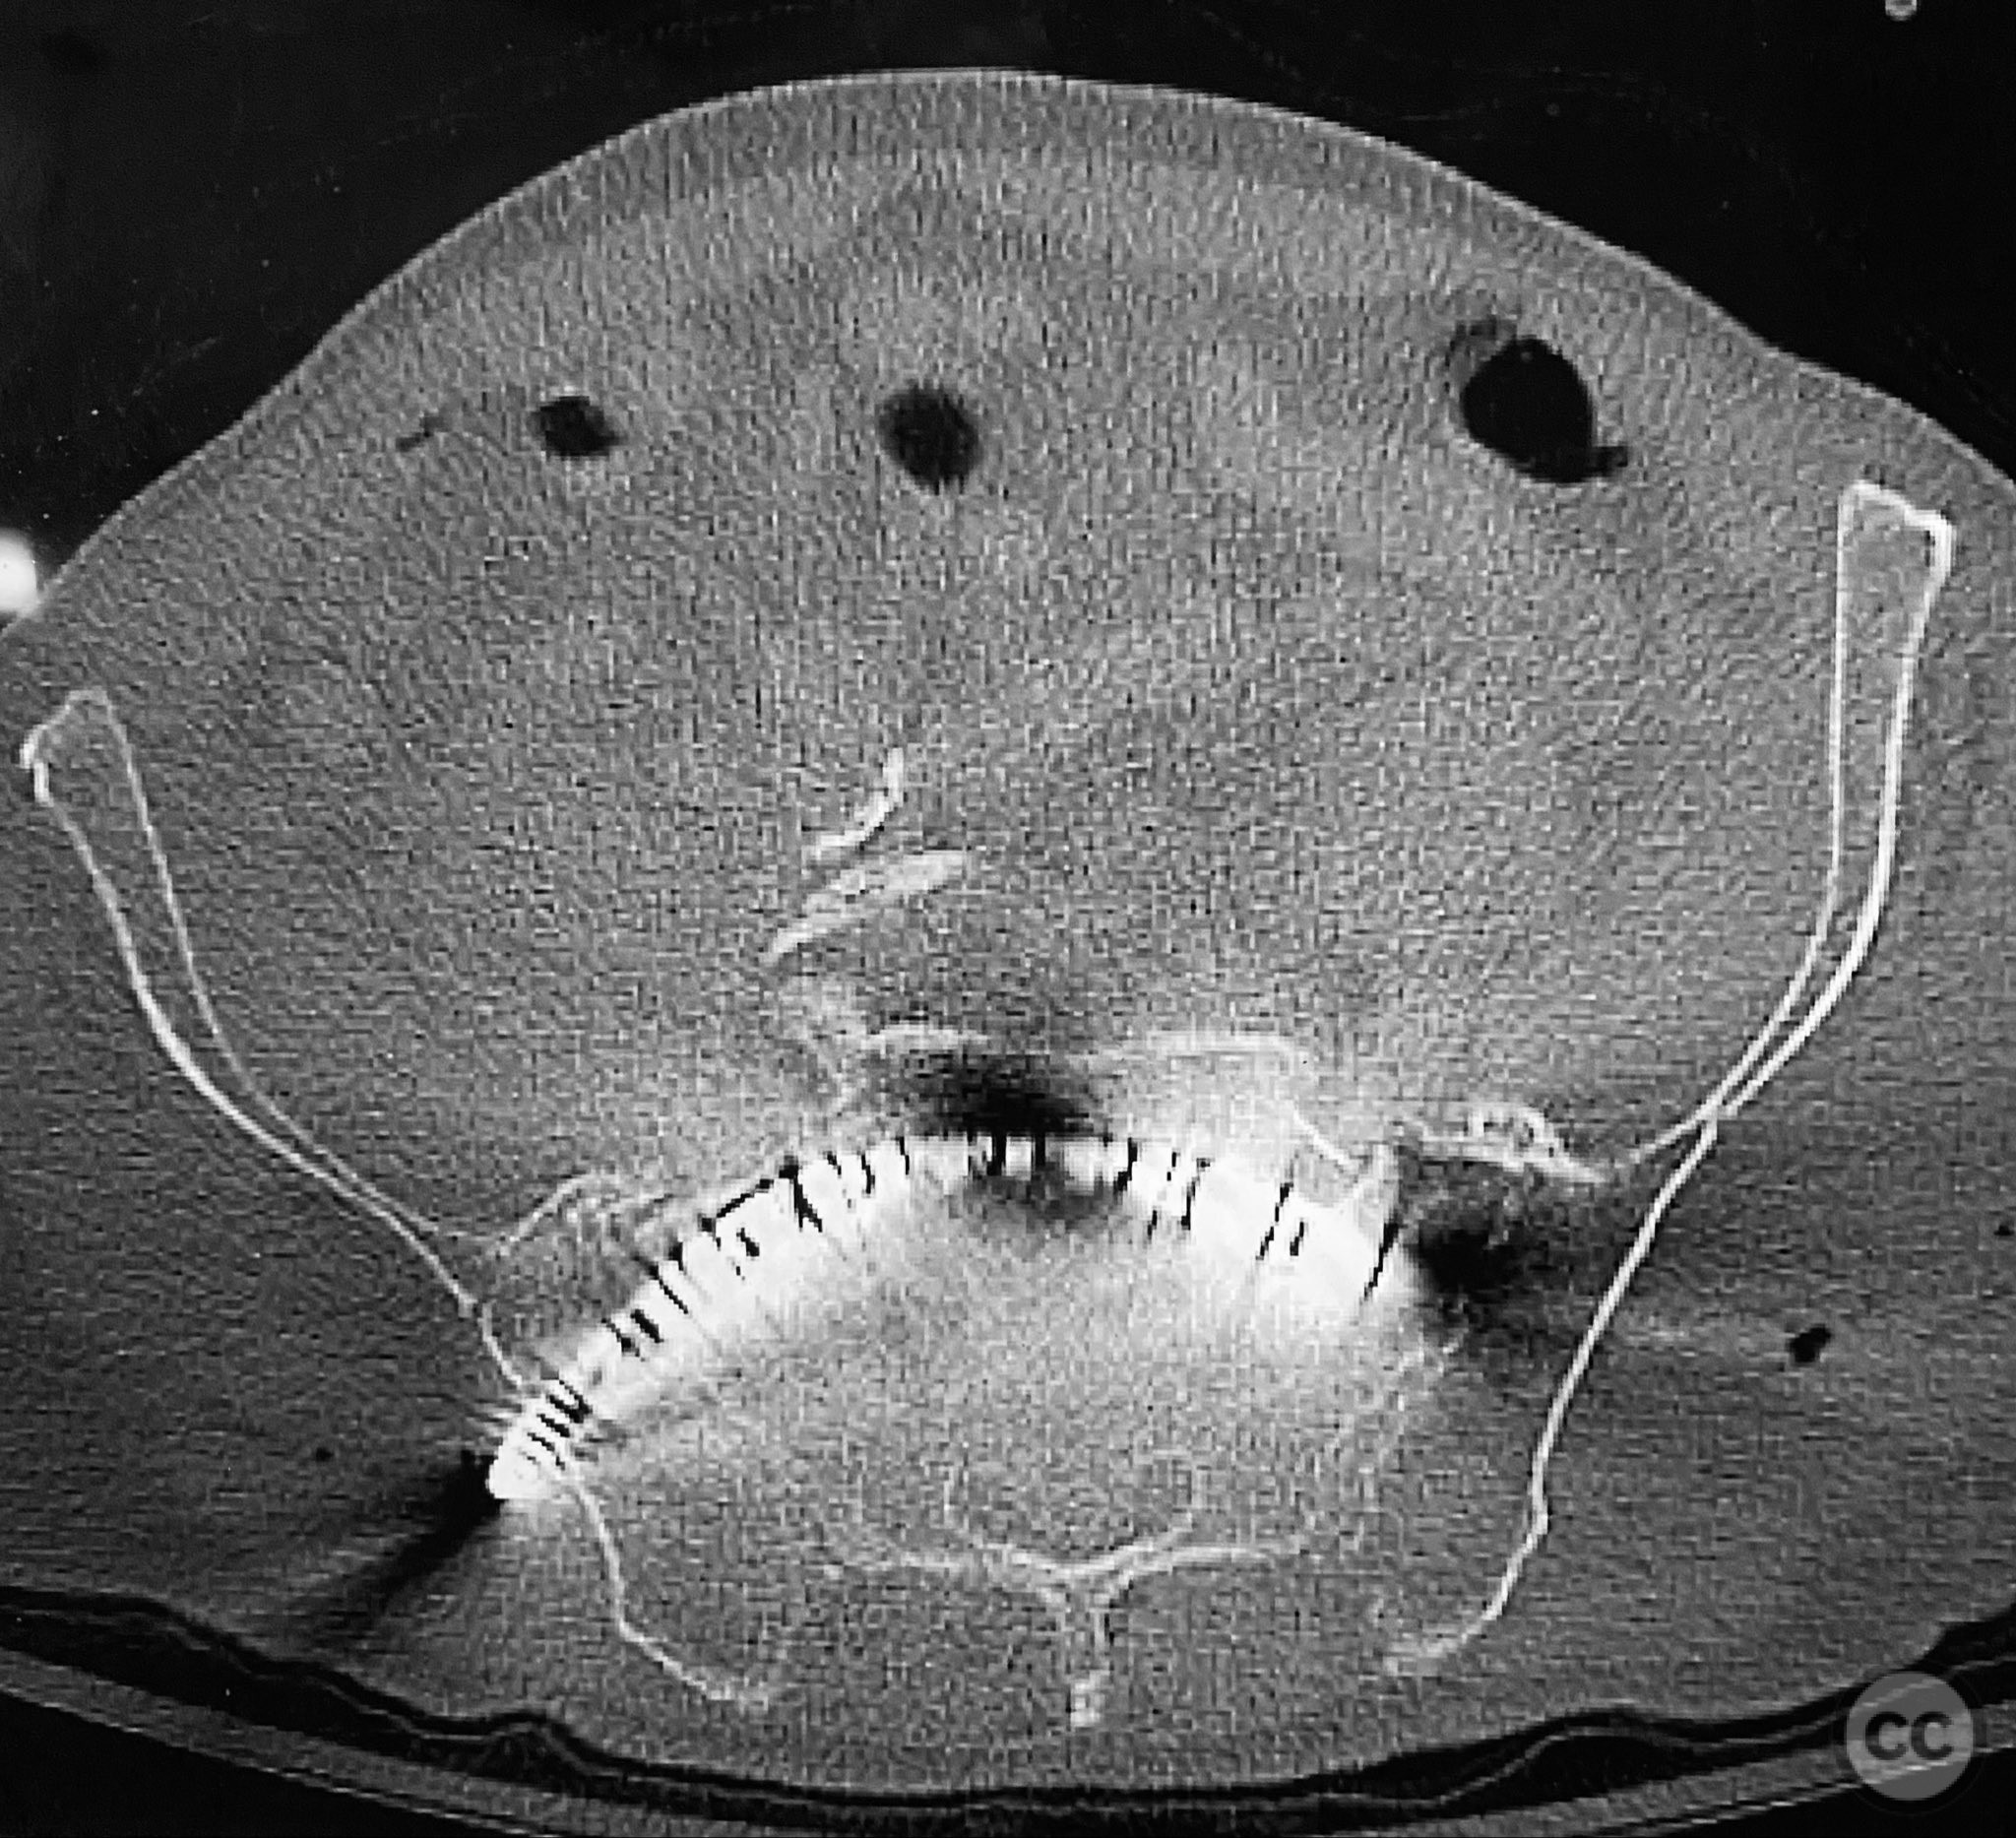

Clinical and radiological findings:  An elderly patient presented with a complex upper sacral fracture characterized by oblique fracture pathways bilaterally, described as a "UYH+pattern" fracture. The patient exhibited compromised bone quality consistent with age-related osteopenia or osteoporosis. Initial clinical assessment prioritized pain control and early mobilization. Radiological evaluation, including computed tomography (CT), confirmed the oblique orientation of the upper sacral fracture lines and their bilateral extension. No neurovascular compromise was reported.

Anatomical surgical approach:  Percutaneous access was established over the dorsal aspect of the pelvis. Small incisions were made lateral to the sacrum, and soft tissue dissection was performed to the level of the os sacrum. Guide pins were advanced under fluoroscopic control along the oblique upper sacral corridors bilaterally. The cannulated CurvaFix device was inserted over each guide pin, articulated to match the oblique fracture pathway, and subsequently locked in situ according to the manufacturer’s specifications.

The articulated nature of the CurvaFix device allowed precise accommodation of the complex oblique upper sacral fracture pathways bilaterally. Percutaneous technique minimized soft tissue disruption and surgical morbidity. Postoperative CT imaging confirmed satisfactory device placement and fracture reduction. The achieved stability provided immediate pain relief, reduced or eliminated narcotic requirements, and enabled early mobilization. Surgeons with experience in device removal have reported no technical difficulties.